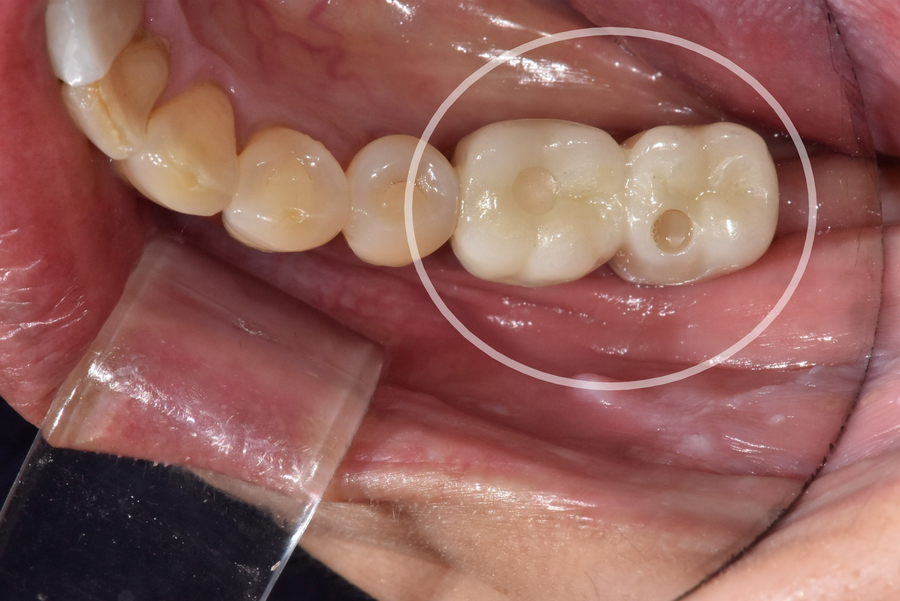

고덕동 치과 230926 왼쪽 아래 어금니 2개 치료

저희 치과에서 왼쪽 아래 어금니 임플란트를 하신

60대 여성 환자분이십니다.

이 환자분은 임플란트 완성 후

검진일에 오지 않으셨다가,

계속 연락을 드려 겨우 뵙게 되었네요.

엑스레이 사진을 통해

임플란트에 문제가 없는지 확인하려는 찰나,

230926 치아 사이 충치

임플란트와 바로 옆 자연치아 틈새에 약간의 충치가

진행되고 있는 걸 발견했습니다.

충치가 심하지 않아

지금 바로 치료하기에는 아까워서,

환자분께 치간칫솔로 관리 잘해주시고

다음 번 정기검진일에 꼭 내원해달라고 말씀드렸던 기억이 납니다.